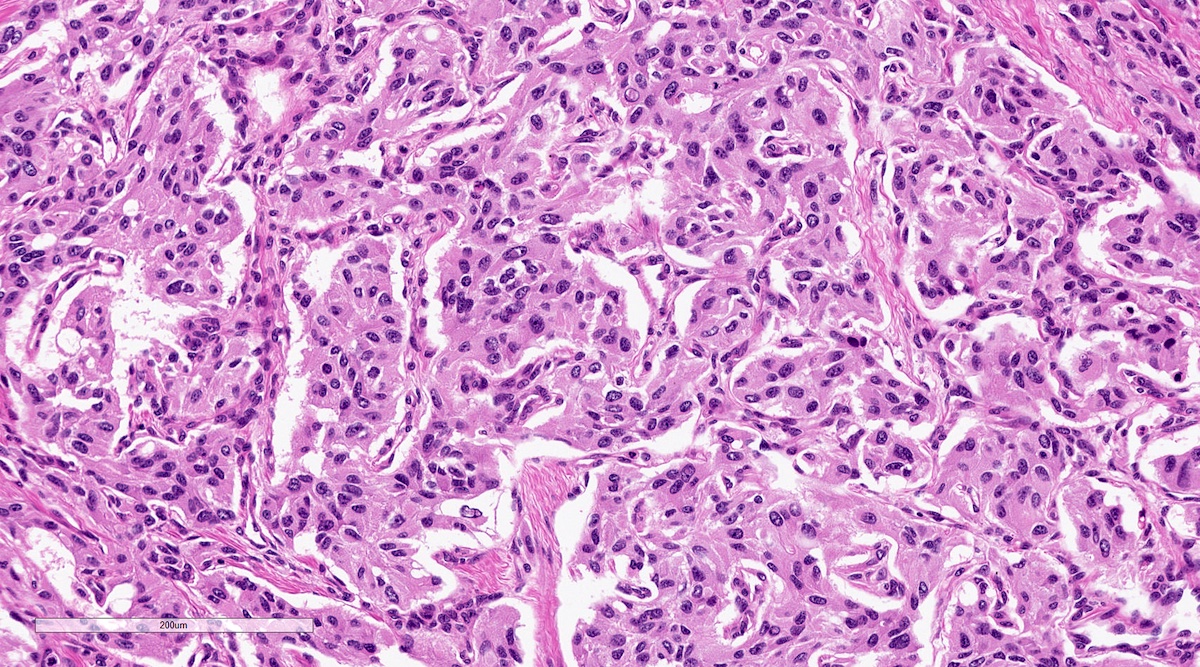

Microscopic (histologic) description

- Prevailing histologic pattern: epithelioid chief cells arranged in distinctive clusters / nests (zellballen pattern), separated by prominent fibrovascular stroma (J Clin Med 2018;7:280)

- Trabecular pattern: ribbons or cords of epithelioid cells divided by fibrous bands

- Other patterns: pseudorosette, angioma-like, spindled and sclerosing

- Chief cells: round, oval to polygonal cells with abundant granular basophilic, eosinophilic or amphophilic cytoplasm (Surg Pathol Clin 2019;12:951)

- Intracytoplasmic hyaline globules may be present in sympathoadrenal paragangliomas

- Giant multinucleated cells and bizarre cells can be present (Srp Arh Celok Lek 2002;130:7)

- Rarely, elongated and spindle shaped cells with a sarcomatoid appearance may be found

- Scattered ganglion cells can be seen

- May have nuclear atypia

- May have dysmorphic vessels, melanin-like pigment (neuromelanin) (pigmented paraganglioma), amyloid, abundant stroma and osseous metaplasia (Diagn Pathol 2012;7:77, Hum Pathol 1992;23:33)

- No or rare mitotic figures except in highly aggressive rapidly proliferating lesions

- May have focal chronic inflammatory infiltrate

- Necrosis is unusual except in patients who have undergone preoperative tumor embolization

- Special histopathologic features usually related to genetic syndromes:

- VHL syndrome: prominent stromal edema, clear cytoplasm and lipid degeneration (Am J Surg Pathol 1987;11:480)

- SDHx related syndrome: granular eosinophilic cytoplasm (Am J Surg Pathol 2020;44:422)

- MEN2 syndrome: unilateral or bilateral adrenal medullary hyperplasia (Neoplasia 2014;16:868)

Microscopic (histologic) images

Contributed by Luvy Delfin, M.D. and Sylvia L. Asa, M.D., Ph.D.